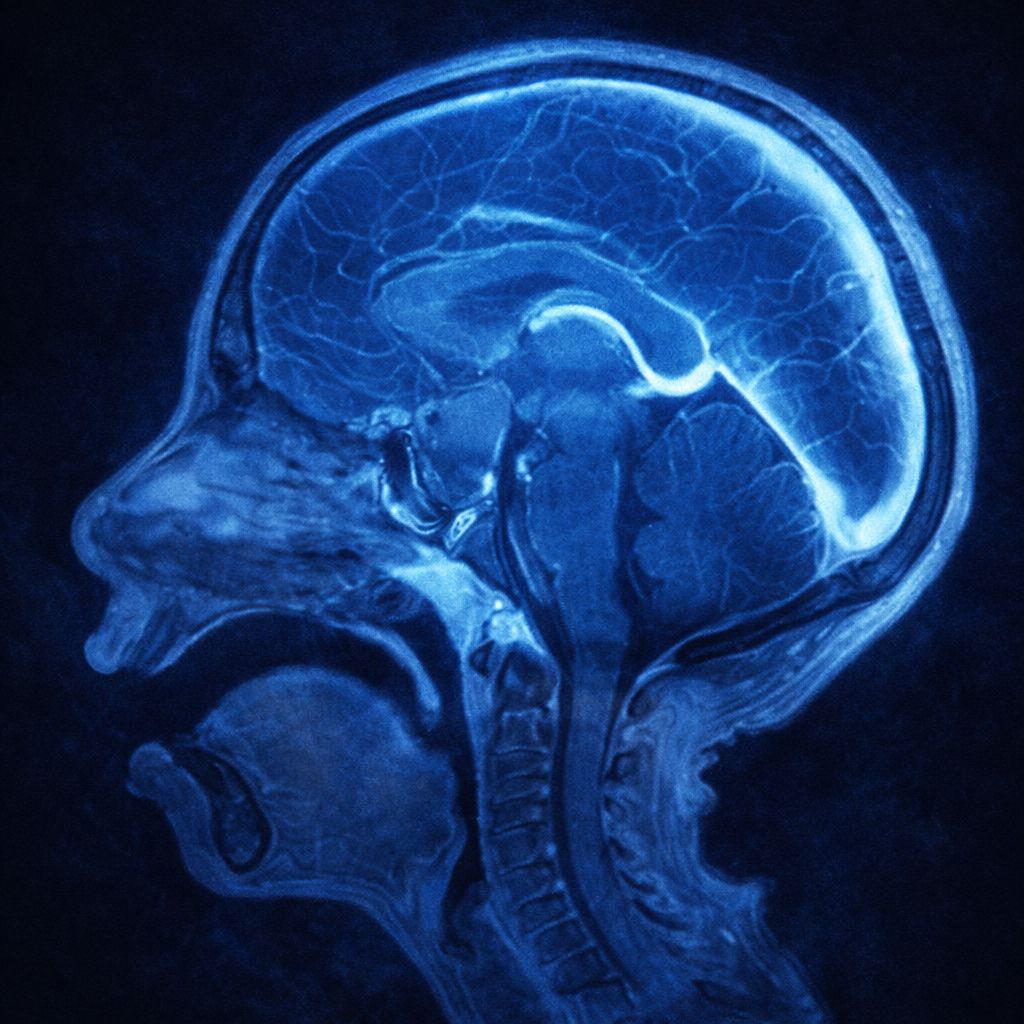

La resonancia magnética es el estudio apropiado para diagnosticar un craneofaringioma, ya que generalmente captan medio de contraste de manera regular, aunque pueden tener grandes componentes quísticos.

En las tomografías, es característico encontrar una tumoración por arriba de la silla turca con calcificaciones.